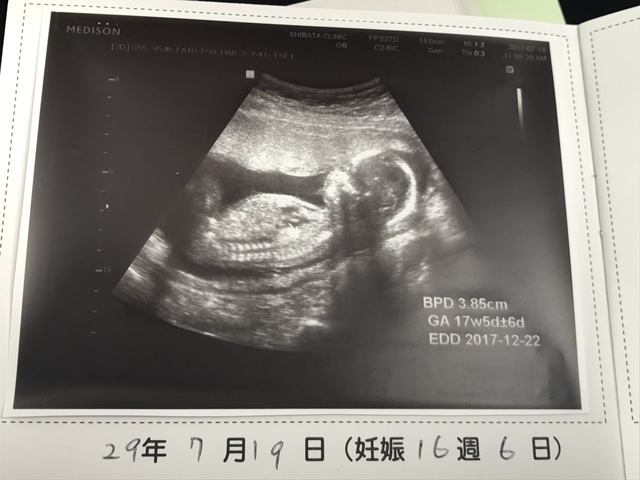

16週0日(16w0d・女の子)|yu0215ki さん(29歳)

エコー写真撮影時のエピソード:

パパも一緒にエコー見た!始めてのお腹からのエコー☆私よりパパの方が興奮してた(^O^)赤ちゃんは元気いっぱいで動き回ってた。手足を伸ばしたりして、背骨もしっかり出来てて順調で安心した( *ˊᵕˋ)

そして、今のところ女の子!でもまだへその緒で隠れてたりするからはっきり女の子とは言えないって^^でも元気で産まれてくれるならどっちでもいいや!